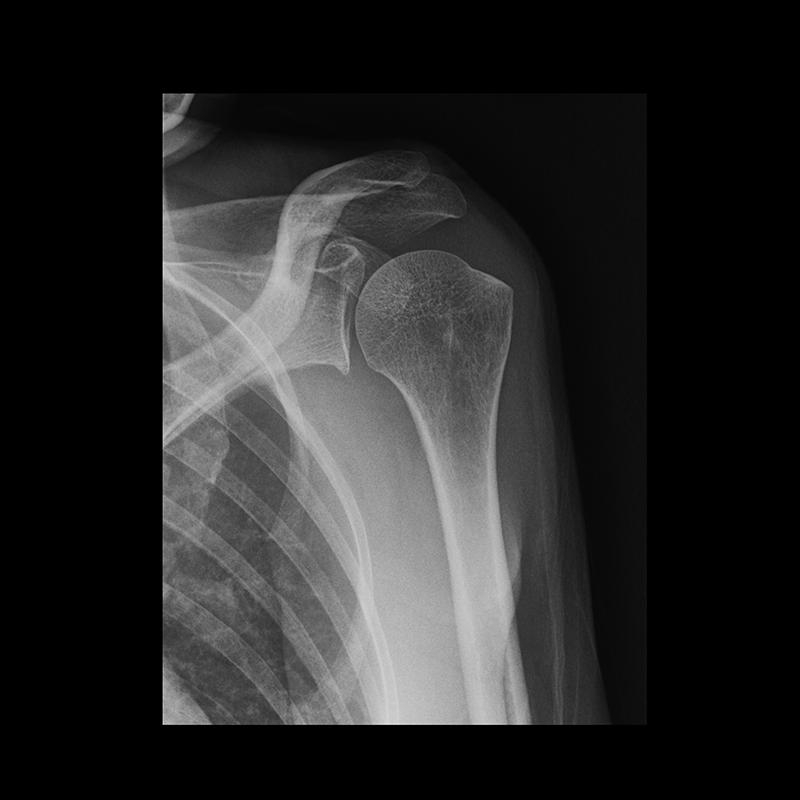

Exame que registra a imagem de ossos, órgãos ou formações internas do corpo utilizando raios X. Os exames de raios x são popularmente conhecidos como expressões, “tirar uma radiografia ” ou “bater uma chapa”.

O raio X serve para avaliar as condições de órgãos e estruturas internas como o pulmão e a coluna, para pesquisar fraturas e para acompanhar a evolução de tumores e doenças ósseas, entre outros.